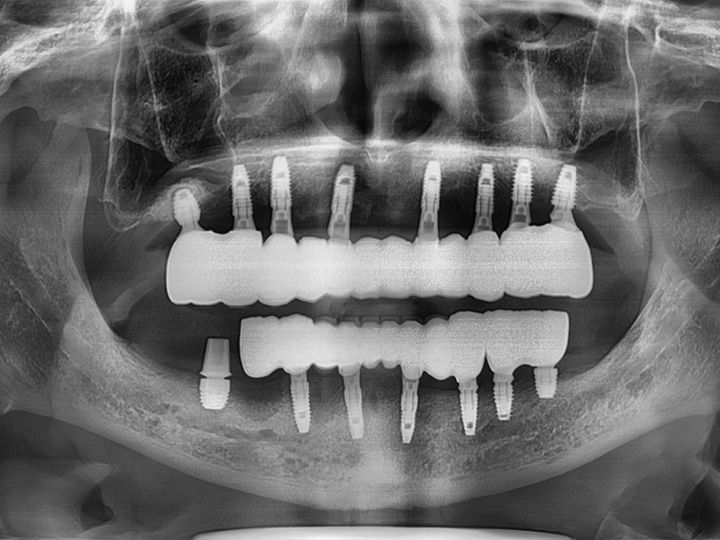

「ライムナム歯科病院」はラミネートやセラミックを使った審美治療、美白治療、インプラント、歯列矯正など、あらゆる歯の悩みに応える歯科病院です。2004年の開業以来、常に新しい技術と診療機器を取り入れ、韓国内外の患者の信頼を集めてきました。特に忙しい現代人の悩みである時間短縮治療メニューが充実。来院当日にできるだけ解決できるようなシステムを構築しています。独自の歯科技工所を持っているのもその理由のひとつ。また20年にわたるノウハウの蓄積を生かし、患者の負担を減らせるように痛みを減らす施術にも力を入れています。